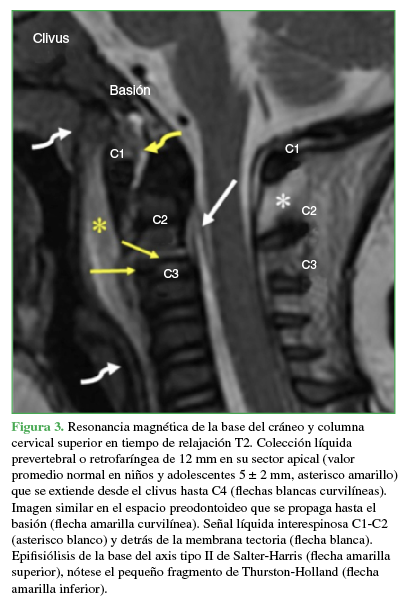

Niña de 9 meses, víctima de un accidente automovilístico. Su madre, sentada en la butaca del acompañante y con el cinturón de seguridad colocado, llevaba a la niña en brazos sobre su falda. Llegó derivada desde otro centro asistencial, con 48 h de evolución. El examen al ingresar reveló un puntaje 13 en la escala de Glasgow, parálisis de ambos miembros superiores con nivel metamérico C5, pero con respuesta a estímulos nociceptivos, indemnidad neurológica de tronco y de miembros inferiores, dificultad respiratoria con neta disminución de la entrada de aire en el hemitórax derecho. Los estudios iniciales incluyeron radiografías de columna cervical y tórax, y resonancia magnética (RM) de ambas regiones.

HALLAZGOS E INTERPRETACIÓN DE LOS ESTUDIOS POR IMÁGENES

En las radiografías anteroposterior y de perfil, de columna cervical, no se observaron anomalías. El trazado de las cuatro líneas sagitales recomendadas en el trauma era normal. Sin embargo, la relación facetaria C2-C3 era dudosa (Figura 1). La disminución de la entrada de aire en el hemitórax derecho se relacionó con una parálisis diafragmática y atelectasia pulmonar masiva (Figura 2). La RM de columna cervical y base del cráneo reveló una epifisiólisis del axis, una lesión ligamentaria posterior y un importante edema perivertebral (Figura 3).